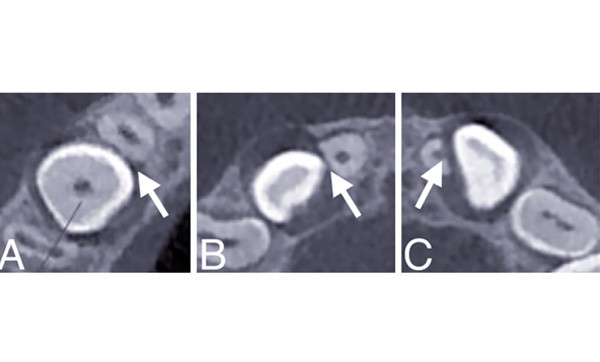

La présence de résorptions radiculaires a été évaluée à l’aide de clichés issus d’un même appareil de tomographie volumique à faisceau conique (CBCT) (fig. 1), et d’éventuels facteurs prédictifs ont été relevés sur ces mêmes images, ainsi que sur les reconstructions curvilignes à partir des données 3D. L’échantillon a été caractérisé à l’aide de statistiques descriptives et des régressions logistiques multiples ont été entreprises afin de prédire les lésions résorptives.

56 canines (67,5 %) étaient à l’origine de résorptions radiculaires dans cet échantillon, touchant 44 des incisives latérales (55,7 %), 7 incisives centrales (8,4 %) et 16 premières prémolaires (19,5 %). 71,7 % de ces résorptions étaient légères. L’existence d’un contact entre la canine et la racine adjacente a constitué le seul facteur de risque statistiquement significatif, toutes dents confondues (OR = 18,7 ; intervalle de confiance à 95 % : 2,26 – 756 ; p < 0,01).

Cette étude vient confirmer d’autres travaux antérieurs. Le diagnostic positif des résorptions légères s’avère toutefois délicat, en raison des limites de résolution spatiale des tomographies volumiques à faisceau conique…